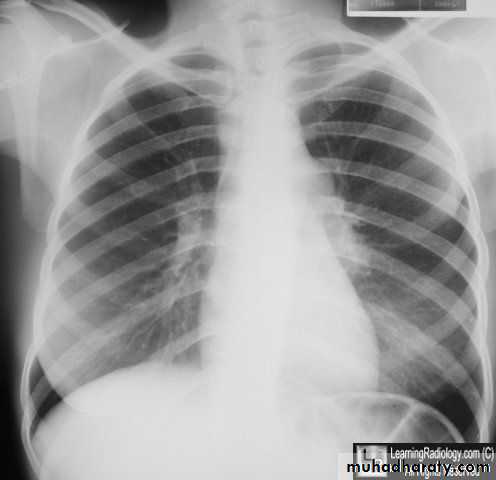

Tuberculosis primary TB